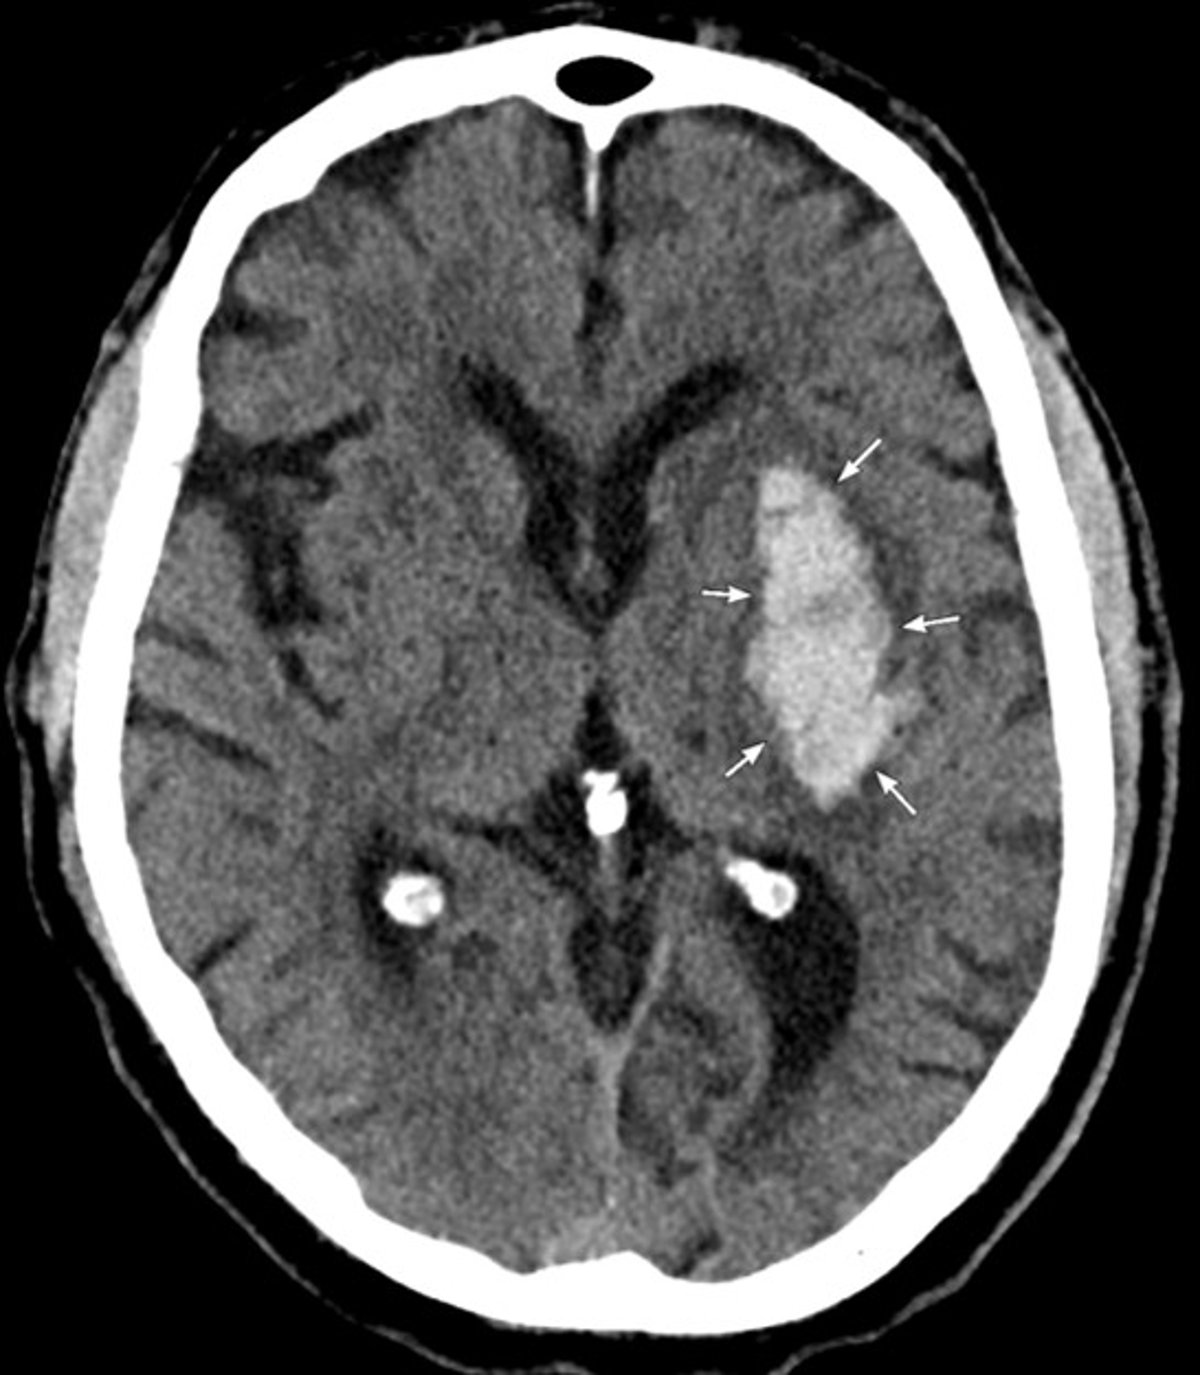

TC de la cabeza

La TC muestra una hemorragia aguda en los ganglios basales izquierdos, que es compatible con una hemorragia intracerebral hipertensiva.

Image courtesy of Mustafa Mafraji, MD.